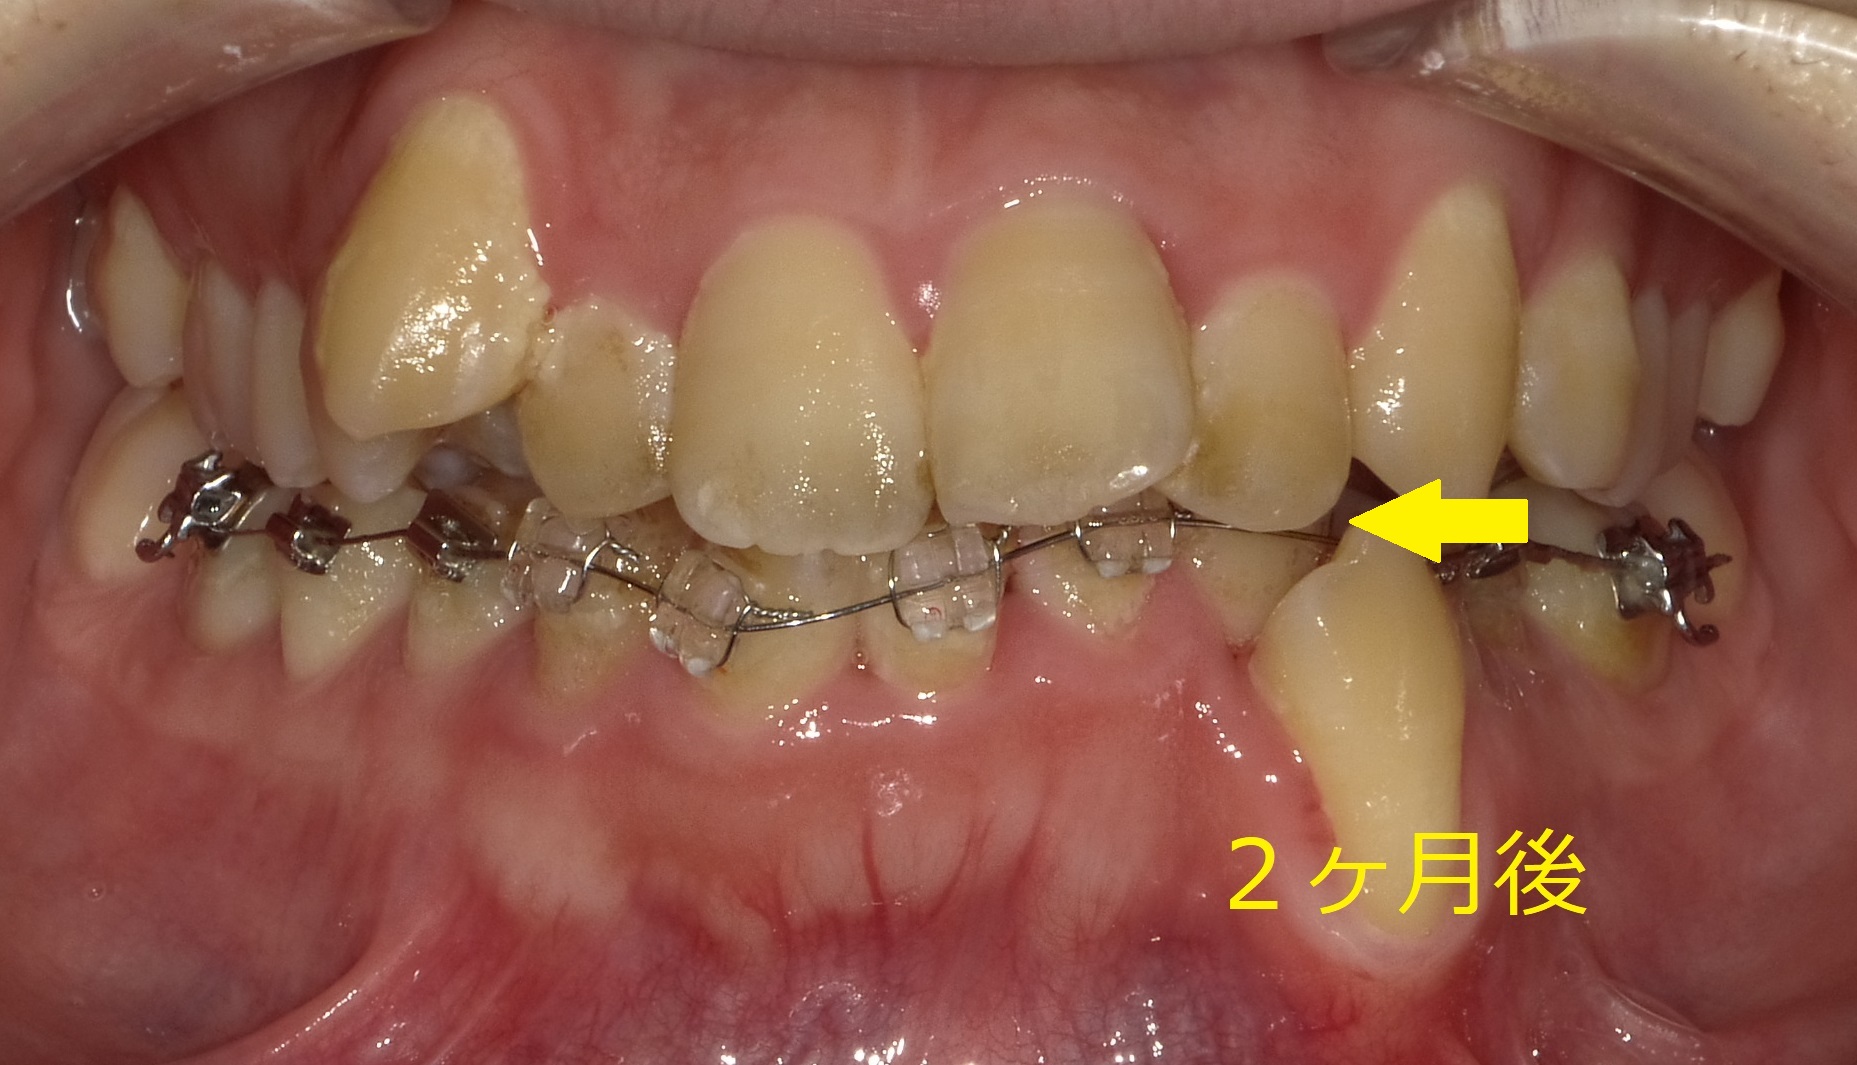

この2ヶ月は奥歯を広げることをメインにしているので前歯の状態にあまり変化は見られませんが、元々左上の2番目と下の八重歯が噛み合っていたのが下の写真の矢印のように、奥歯が立ち上がることによって当たらなくなってきています。

※写真の状態は奥歯をしっかり噛ませている状態です。